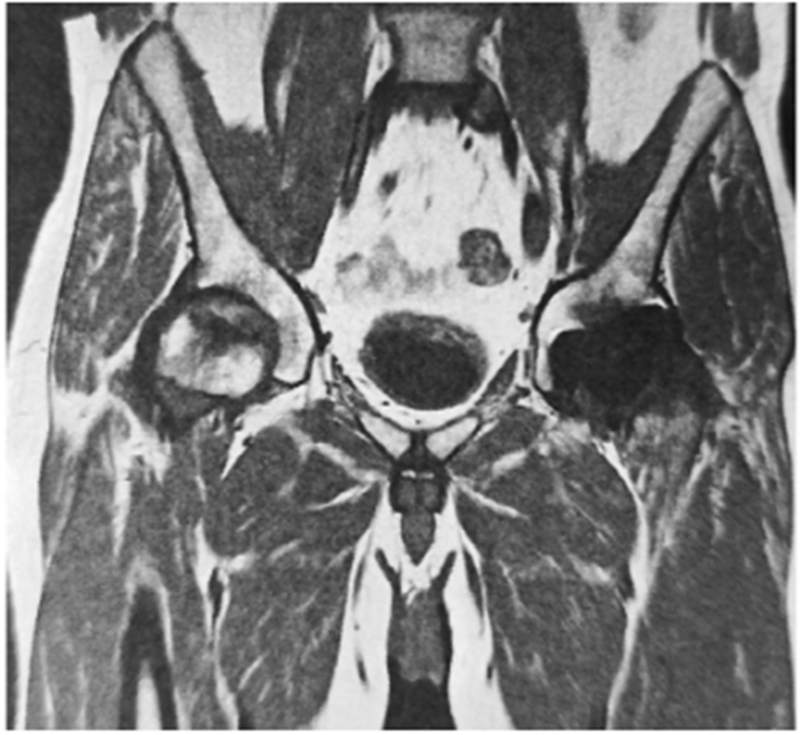

图2 同一患者术后一年双髋核磁,无并发症